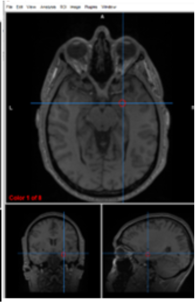

lateral ventricles

circulate and produce cerebrospinal fluid

thalamus

filters information, regulates conscoiusness and sleep